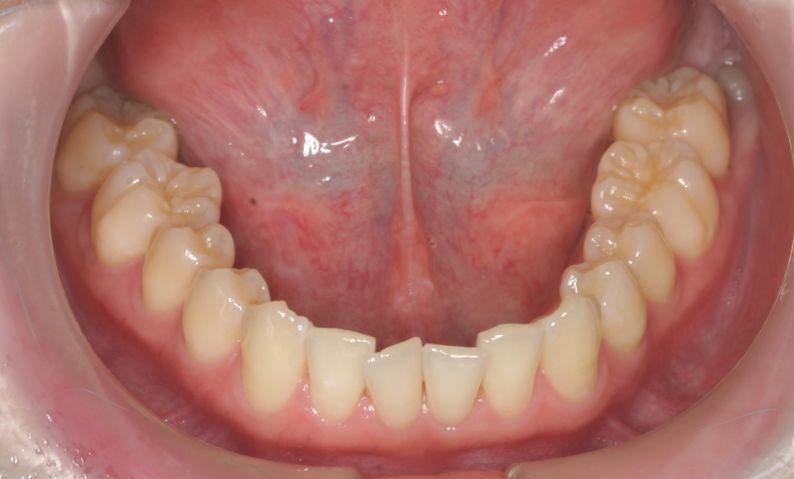

Case 2

主訴:  噛みにくい

診断:  アングルⅠ級 叢生

治療方針:

患者さんは26歳の女性で、上下顎の叢生による審美障害と咬合異常を訴えた。セファロ分析の結果、U-1 to FHおよびL-1 to Mandibularは1S.D.を超えて小さい値であった。その為、上下顎の叢生量は大きいが、上下前歯部の舌側傾斜による口元の落ち込みを防止する目的で、非抜歯で治療を行うことにした。

治療期間: 1年4カ月

費用:

診断費30000円、装置費用600000円、保定装置費用50000円、月1回の調整費4000円  (全て税別)

【 治療前 】

【 治療後 】